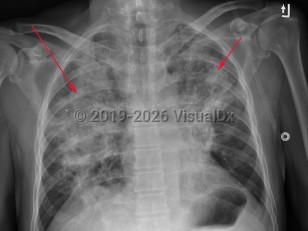

EVALI